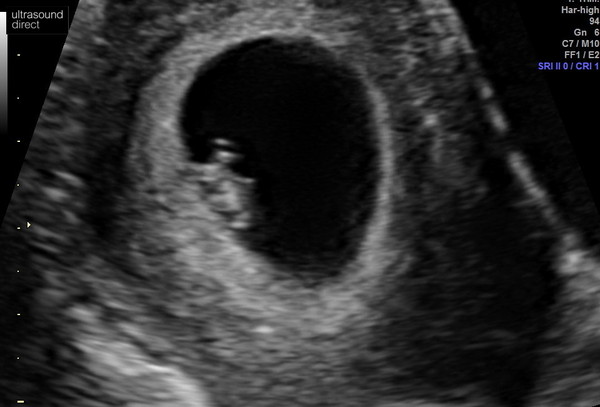

ellie1789 · 20/12/2021 16:48

Forgot to attach the image

Just had my first scan and was dated at 7+1, so 4 days ahead of what I thought I was. It was perfect! Heart pumping away, yolk sac a good size and in place, no lumps or bumps that shouldn't have been there. I can see it's arms and face on the video that they sent me. I'm thrilled! It definitely feels more real now and I'm relieved that I'm more ahead than I thought. Also, mine was an external scan which I was surprised at

@ellie1789 mine was an external scan and your is so much clearer. I was only 6 weeks. Just shows you the difference 1 week can make.

@Aims1991 that was the best photo of the bunch. It was hard to see in parts and looked like a wiggly eel on most of the photos, so I must have been the same as you